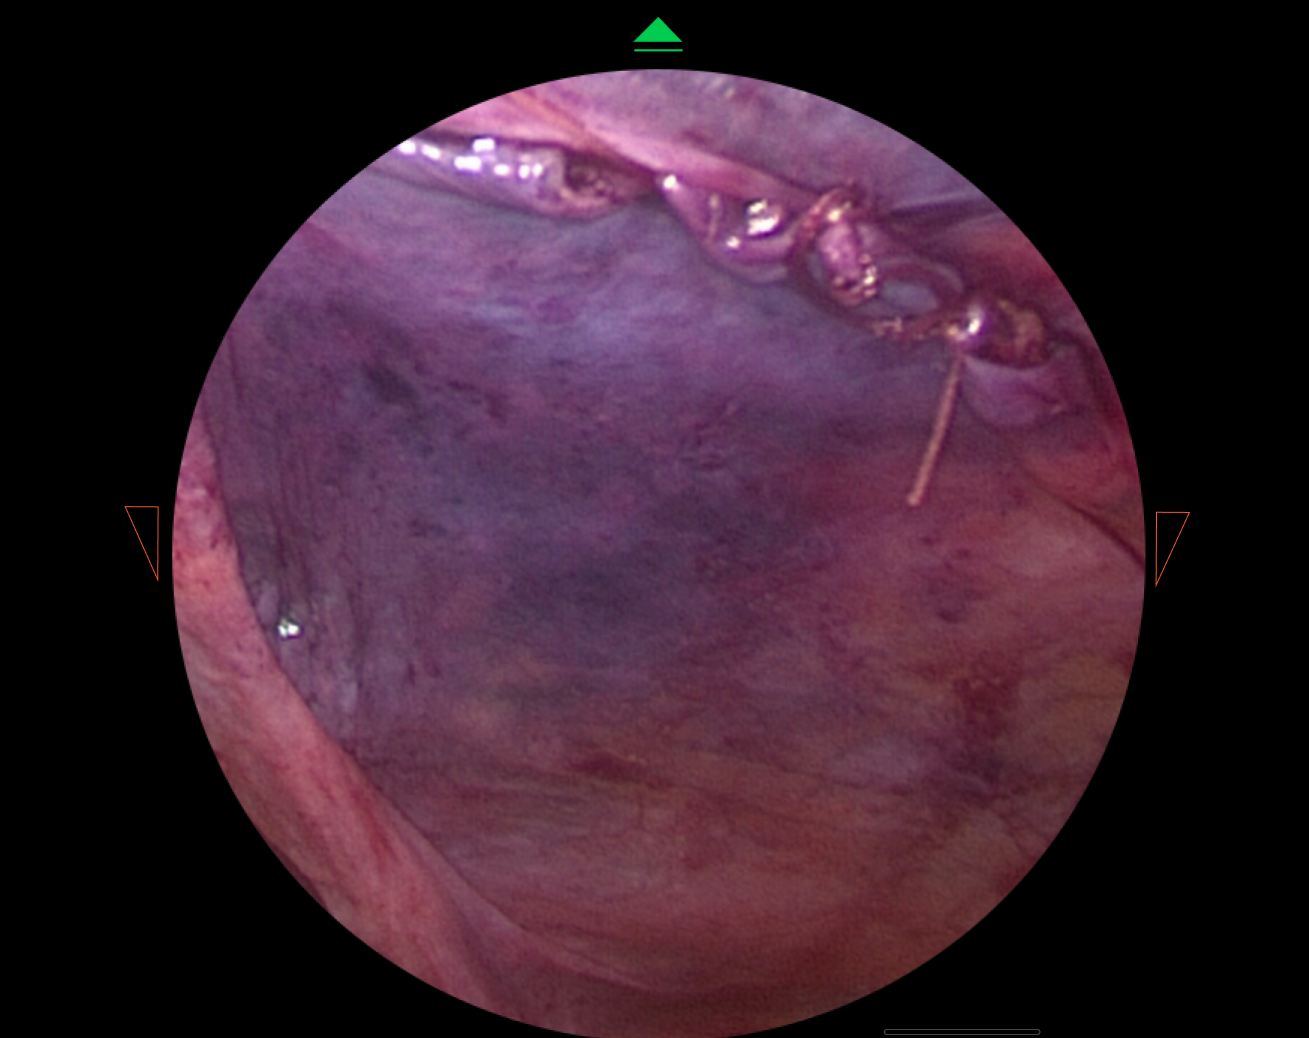

Watch how I brought digital designs to life with real medical hardware

HUD Design: Surgery-Ready Interfaces

Operating rooms aren't like offices. I designed interfaces specifically for heads-up displays, considering lighting, distance, and the critical nature of surgical procedures.